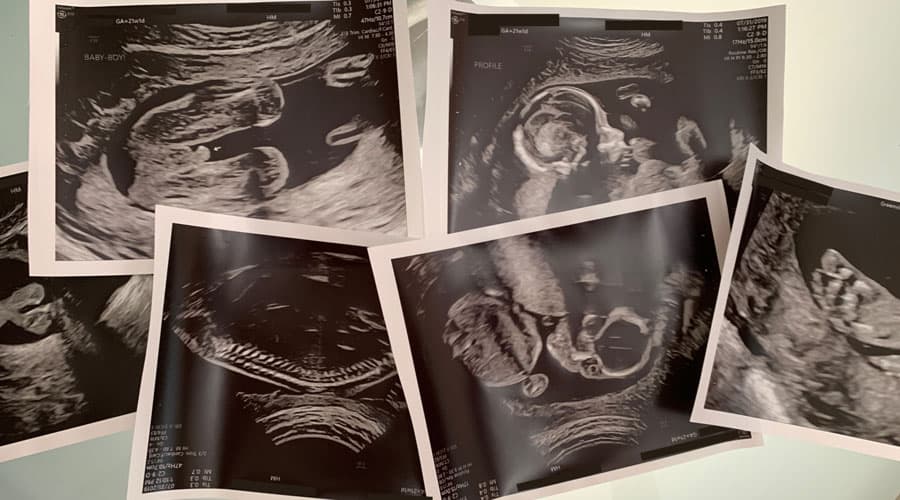

When we were getting our Week 21 ultrasound, our OB went through all the numbers and said everything was looking good. At the very end of the appointment, she casually mentioned that we had a “marginal cord insertion” (not to be confused with a velamentous cord insertion).

Our midwives see this a fair amount (it happens in ~7% of pregnancies), and said they wouldn’t even worry about it at this point, which is pretty much the same stance the high-risk OB took. All it means for us right now is that we have to have a few extra ultrasounds — which has the added bonus of a few extra opportunities to see our little one!